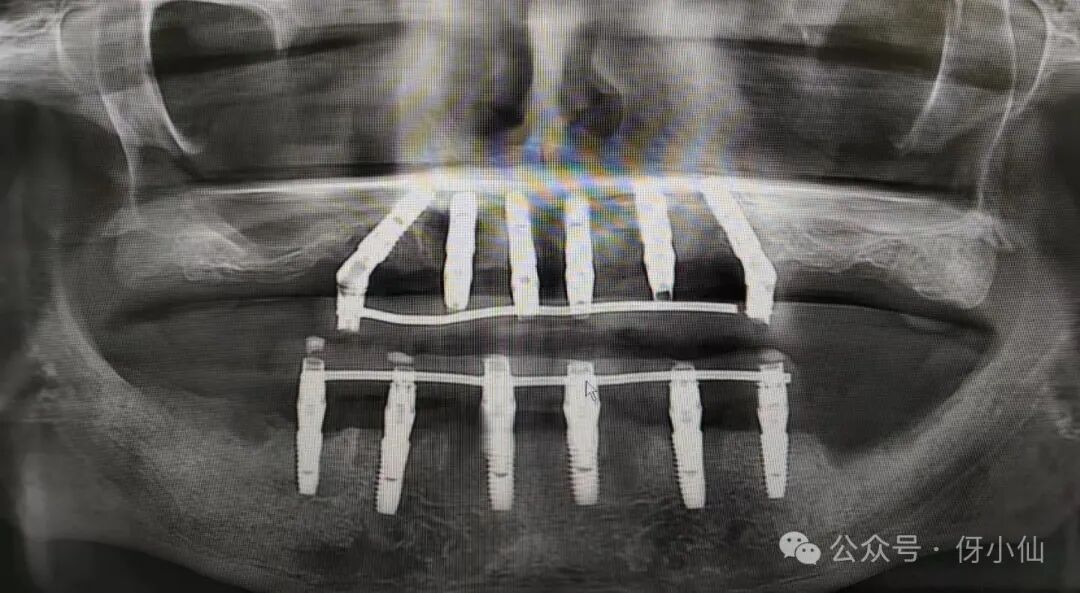

半全口种植是目前口内牙齿全部松动或缺失等的一种流行种植修复方式,通常情况下采取种植4-8颗(半口)或8-16颗(全口)种植牙根修复半口或全口缺失牙!

今天接诊一个半口种植的患者,问为啥不同地方半口或者全口差价那么多呢,有的说大几千就可以,有的说得好几万!价格差距大的第一个原因是种植的牙根品牌不同,越好的品牌,种植半口或者全口就会越贵!另一个主要原因是上部修复牙冠桥体方式不同,导致价格也会不同!当下上部修复全瓷牙冠桥体方式主要有三种:

1:马泷桥架(当下推荐的主要修复方式,万一有牙冠崩瓷或损坏可不必全部拆除,哪里坏修哪里就好,整体也好拆卸,价格偏贵)

2:钛支架氧化锆(如果一颗牙齿崩瓷或者损坏需要整个桥体牙齿全部拆除返修,会有暂时缺牙期,好在拆卸方便,价格相对居中)

3:个性化基台+全瓷桥体(如果一颗牙齿崩瓷或损坏需要整个牙齿全部拆除从新制作,而且拆卸麻烦耗时,会有暂时缺牙期,价格相对便宜)